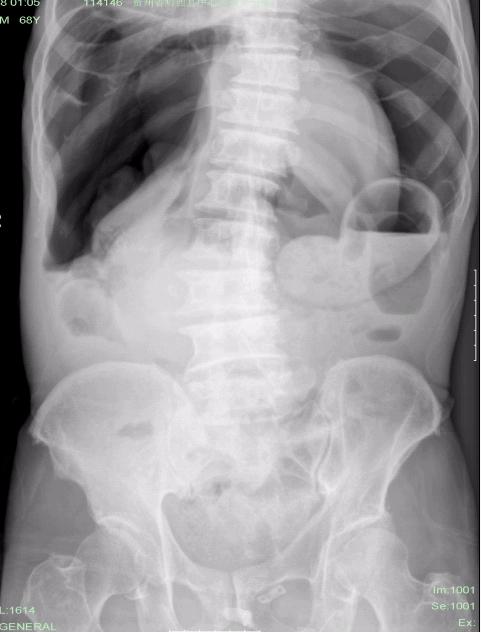

男,68岁,腹痛20多天。

气腹?..........我还以为肠梗阻呢?张力那么高!!!不要搞错了浪费病人的病情就行~~~~~

气腹,见宽大气液平, 太恐怖啦吧。

气腹,除了胃肠道穿孔外,还应考虑:肠壁气囊肿症

机械性梗阻和营养失调同时存在时易产生肠气囊肿症。常见于溃疡病。在正常情况下,淋巴液内碱性碳酸盐与胃肠道内发酵的酸性产物接触即分解出二氧化碳,二氧化碳又被血中氮气所代替,而使气体进入淋巴管中。在溃疡病合并幽门梗阻病人,因产生的二氧化碳较多,胃内压力增高,蠕动亢进,易将淋巴管内的气体压至粘膜下或浆膜层而形成气肿。表现为链条状、串珠状透亮影,当肠壁气囊肿破裂时,气腹气量多少不等,可中量到大量。临床上病人感到腹胀不适而来院诊治,但常误诊为急腹症而收治入院-------摘自《急腹症影像学》

本例的临床症状是腹痛20天,应考虑肠壁气囊肿症的可能,建议检查消化道,有无溃疡病

典型的大量气腹----消化道穿孔。

大量气腹。考虑胃肠穿孔可能。

大量气腹;多为腹部空腔脏器穿孔所致。